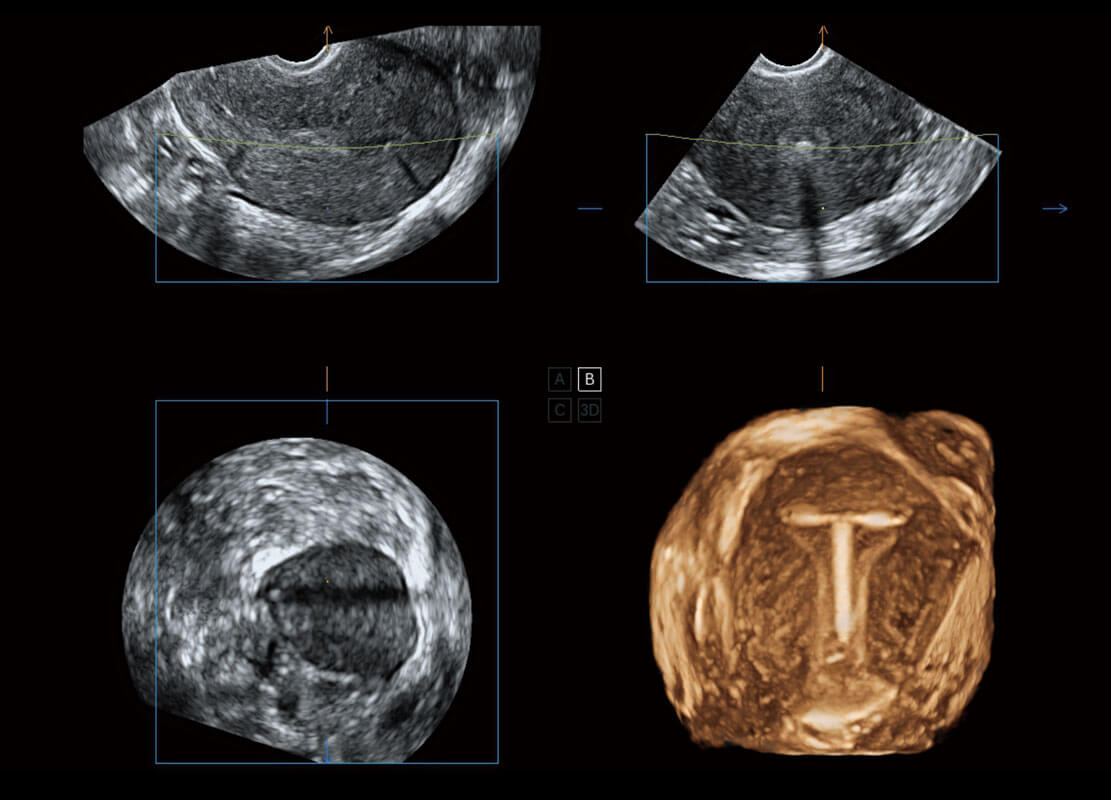

腔內(nèi)三維-宮內(nèi)節(jié)育器

腔內(nèi)三維-光影成像